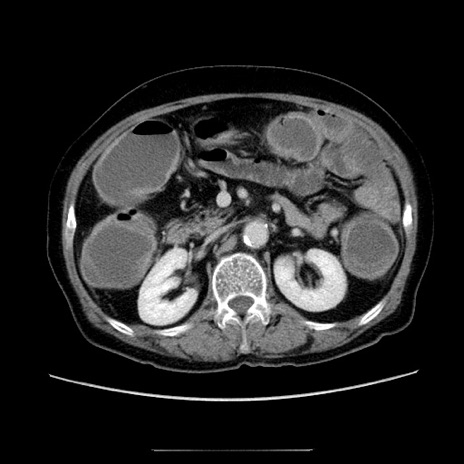

症例5(横断像)

【症例】70歳代女性

【主訴】お腹が張る

【現病歴】1週間くらい前から腹部膨満の自覚あり。昨日夜から増悪したため、本日救急外来受診。

【身体所見】意識清明、BT 36.5℃、BP 165/106mmHg、HR 80bpm、SpO2 98%、腹部:膨満、軟、自発痛・圧痛なし、触診にて不快感あり、腸蠕動音:減弱

【データ】WBC 12600、CRP 1.04